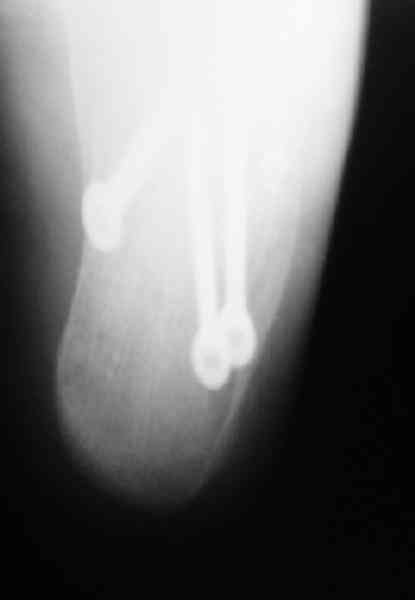

Открытый и закрытый способы лечения.